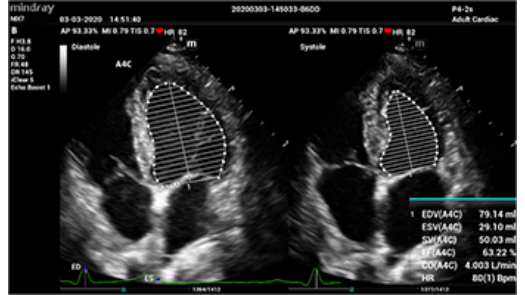

?? ?? ??

? ????? ??

? ?? ??? ?? ??